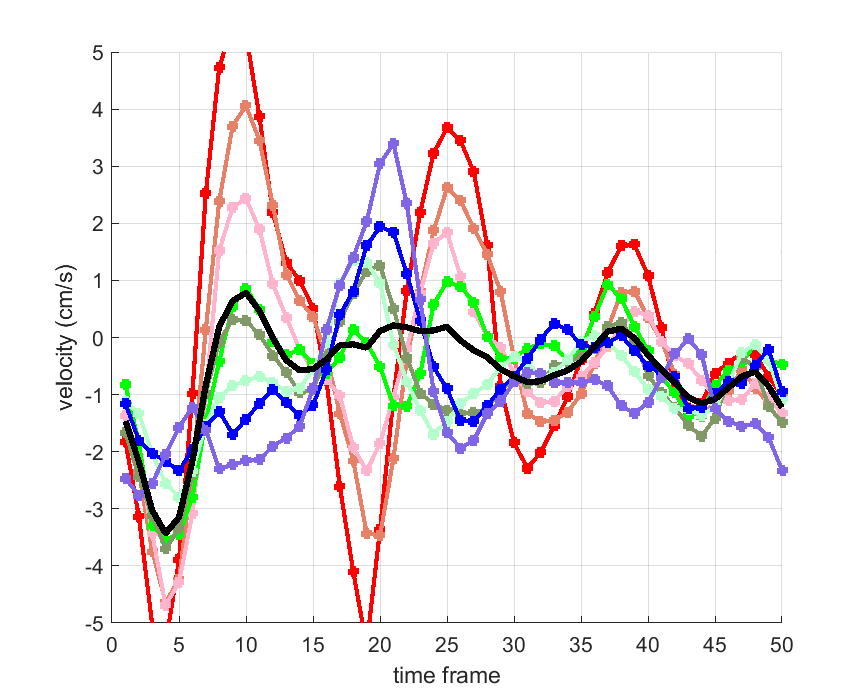

Time courses of the estimated translational component per subject, frame, slice and volume along the 3 velocity directions x, y and z are presented in Fig.6 - Fig.8.